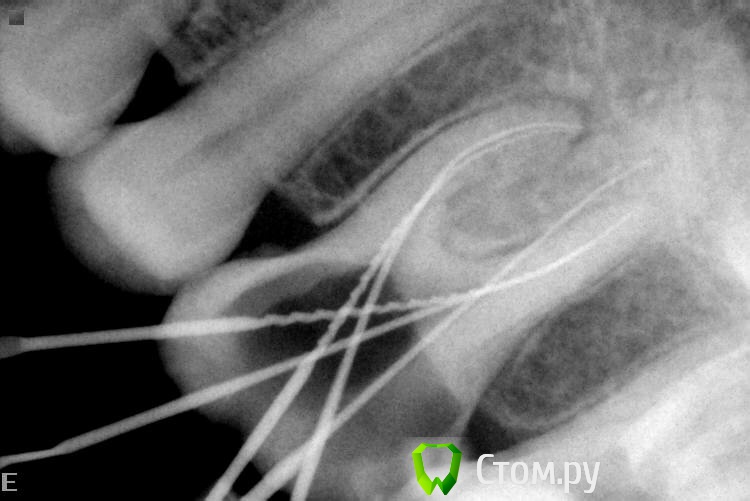

Slaggy Опубликовано 6 ноября, 2014 Автор Поделиться Опубликовано 6 ноября, 2014 Кейс некрасивый. Но какой уж есть.За качество снимков дико извиняюь. Мой рекордсмен: Пациент обратился по гарантии в клинику. 16ый зуб. Жалобы периодонтитные.снимок 2 месяца назад - Пломба поразила своей оригинальностью ((( - не суть.нашел каналы - временная пломба - Запломбировал - Шесть каналов - 3 в МВ системе, 2 в DB и небный. Вернул нашлепку на место. Обычно отправляю к доктору - виновнику торжества на пломбировку, но тут решил, что через недельку обточу и коронку, потому что МОД полость, глубоко, пломба - на снимке во всей красе. Если полностью убрать и переделать - все одно под коронку.Снимки без коффера, сделаны после снятия оптрадама. 4 Ссылка на комментарий